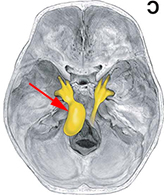

症例2) 38歳女性、左三叉神経鞘腫、外科治療のみ

< 画像所見 >

右三叉神経部に大きな腫瘍あり。

< 手術所見 >

ナビゲーションシステムの使用

< 術後画像所見 >